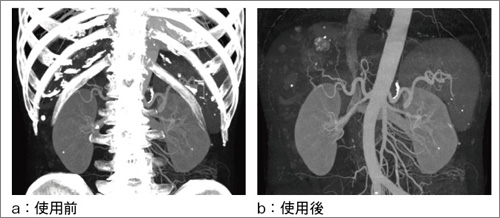

MiP(Maximum Intensity Projection)像は,病変と脈管との関係の情報を得るために必須の画像であるが,いかに簡便に骨抜きを行うかが問題となる。

しかし,AWではAuto Remove Bone機能により骨の解剖学的な形状を認識し,ボタンワンクリックにて骨削除を可能にした(図6)。

図6 Auto Remove Bone機能 |